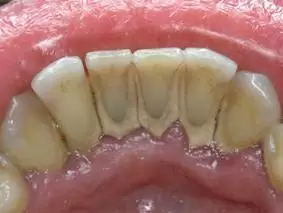

За своєю суттю зубний камінь, це твердий і міцний зубний наліт, що утворюється на зубах і в піддесневих просторах внаслідок поганої гігієни ротової порожнини. Він складається з дрібних залишків їжі та бактерій. Виходячи з цього, можна зробити висновок, що зубний камінь є першопричиною більшості захворювань ясен, таких як гінгівіт і пародонтит, а також самих зубів, – карієс і його ускладнених форм, таких як пульпіт і періодонтит.

При недостаточной гигиене полости рта и самих зубов, зубной налет кальцифицируется и преобразовывается в камень. Отвердевший налет оседает под десны, в результате этого десна отслаивается от поверхности зуба на несколько миллиметров и образуется так называемый патологический карман. В свою очередь, бактерии зубного камня вызывают воспаление десен, что приводит к болевым ощущениям, кровоточивости, покраснению и припухлости десен. Так же появляется неприятный запах изо рта, как следствие разложения продуктов распада жизнедеятельности бактерий присутствующих в камне.Лечение кариеса